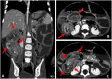

Acute intestinal intussusception remains a surgical emergency in infants and young children aged 3 months to 3 years. It results from the incarceration of the upstream intestinal segment in the downstream segment. In the majority of cases it is idiopathic, but can be secondary to certain pathologies notably Meckel's diverticulum. The site is most often ileo cecal. The symptomatological triad is made up of pain, vomiting, and rectal bleeding. The diagnosis is confirmed by imaging, dominated by ultrasound which remains the reference imaging. We report the case of a 3 year-old boy, followed for a malformation who presented with abdominal distension, abdominal pain, and rectal bleeding. The diagnosis of acute ileo-ileal intussusception was made. After an attempt at hydrostatic reduction under ultrasound guidance, he underwent surgical management. The postoperative period was simple and uncomplicated. Intestinal intussusception remains a pathology with a low morbidity and mortality rate of 0% to 1% due to delayed diagnosis and delayed therapeutic management.